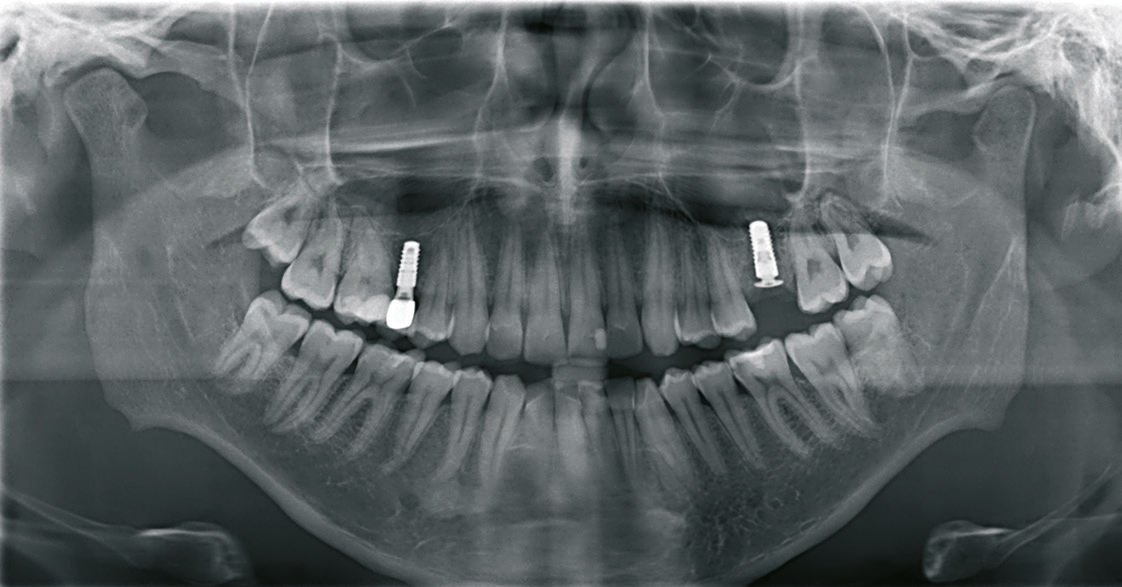

Nach der Präparation des Weichgewebes wurde ein Mukoperiostlappen mit Hilfe der Instrumentenspitze PR2 (Piezosurgery, Mectron, I-Genua) vorsichtig präpariert, um eine suffiziente Deckung der Wunde zu gewährleisten (Abb. 9 und 10). Nach Vorbereitung des Weichgewebes wurde die 3D-gedruckte Bohrschablone auf den Zahnbogen gesetzt und ein Führungsschlüssel mit 2 mm Durchmesser eingesetzt, durch den ein Osteotom einführt wurde, um eine Führung für den nachfolgenden Trepanbohrer in den Knochen kondensierend zu präparieren (Abb. 11). Entlang des Führungskanals wurde das Bett für den allogenen Knochenring (maxgraft bonering; botiss biomaterials GmbH, Berlin) trepaniert (Abb. 12). Der allogene Knochenring wurde extraoral passgenau zugeschnitten und anschließend in die Extrationsalveole platziert (Abb. 13 und 14). Mittels eines breiten Osteotoms wurde der Knochenring samt basalem Knochensegment schablonengestützt nach apikal in den Sinus maxillaris verschoben. Ein parallelwandiges Implantat (Bone Level Roxolid, SLActive, Straumann) mit einem Durchmesser von 4,1 mm und einer Länge von 10 mm wurde zentral in den positionsstabilen Knochenring primärstabil inseriert, mit einer Fixierungkappe (Durchmesser 5,5 mm) versehen und die umliegende Extrationsalveole mit granulärem bovinem Knochenersatzmaterial ausgefüllt (Abb. 15-17). Anschließend wurde die Wunde mit dem Mukoperiostallappen gedeckt und speicheldicht vernäht (Abb. 18). Zur postoperativen Kontrolle wurde ein Orthopantomogramm aufgenommen, auf dem keinerlei Verletzungen benachbarter anatomischer Strukturen zu erkennen sind (Abb. 19). Es folgten zwei radiologische Verlaufskontrollen, vier und sechs Monate nach dem Eingriff, ohne Besonderheiten (Abb. 20 und 21).

Eine Verlaufskontrolle acht Monate nach Versorgung des Implantats zeigte keine Veränderungen und somit stabile Verhältnisse (Abb. 24).